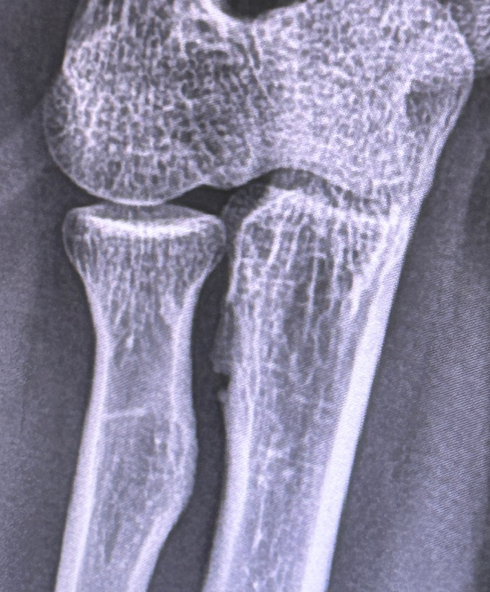

2. 최근 pt헬스 중 팔 통증이 심해져 새 정형외과를 방문하였고 x레이에서 척골 뼈 결손이 발견되어 mri촬영(조영제,1.5t촬영)

5. 서울 아산 병원 진료에서 mri는 정상소견 나옴. 뼈결손도 너무 작아서 종양이라고 보기 어렵다고 얘기함. 추가 ct및 뼈스캔 진행중